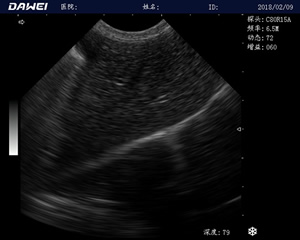

MT15獸用B超機適用探頭

牛羊馬豬犬貓及多種家禽、實驗動物、野生動物、及部分水生動物

中小動物的肝、膽,脾、腎、膀胱、子宮、妊娠等各組織器官的檢查和病變的診斷